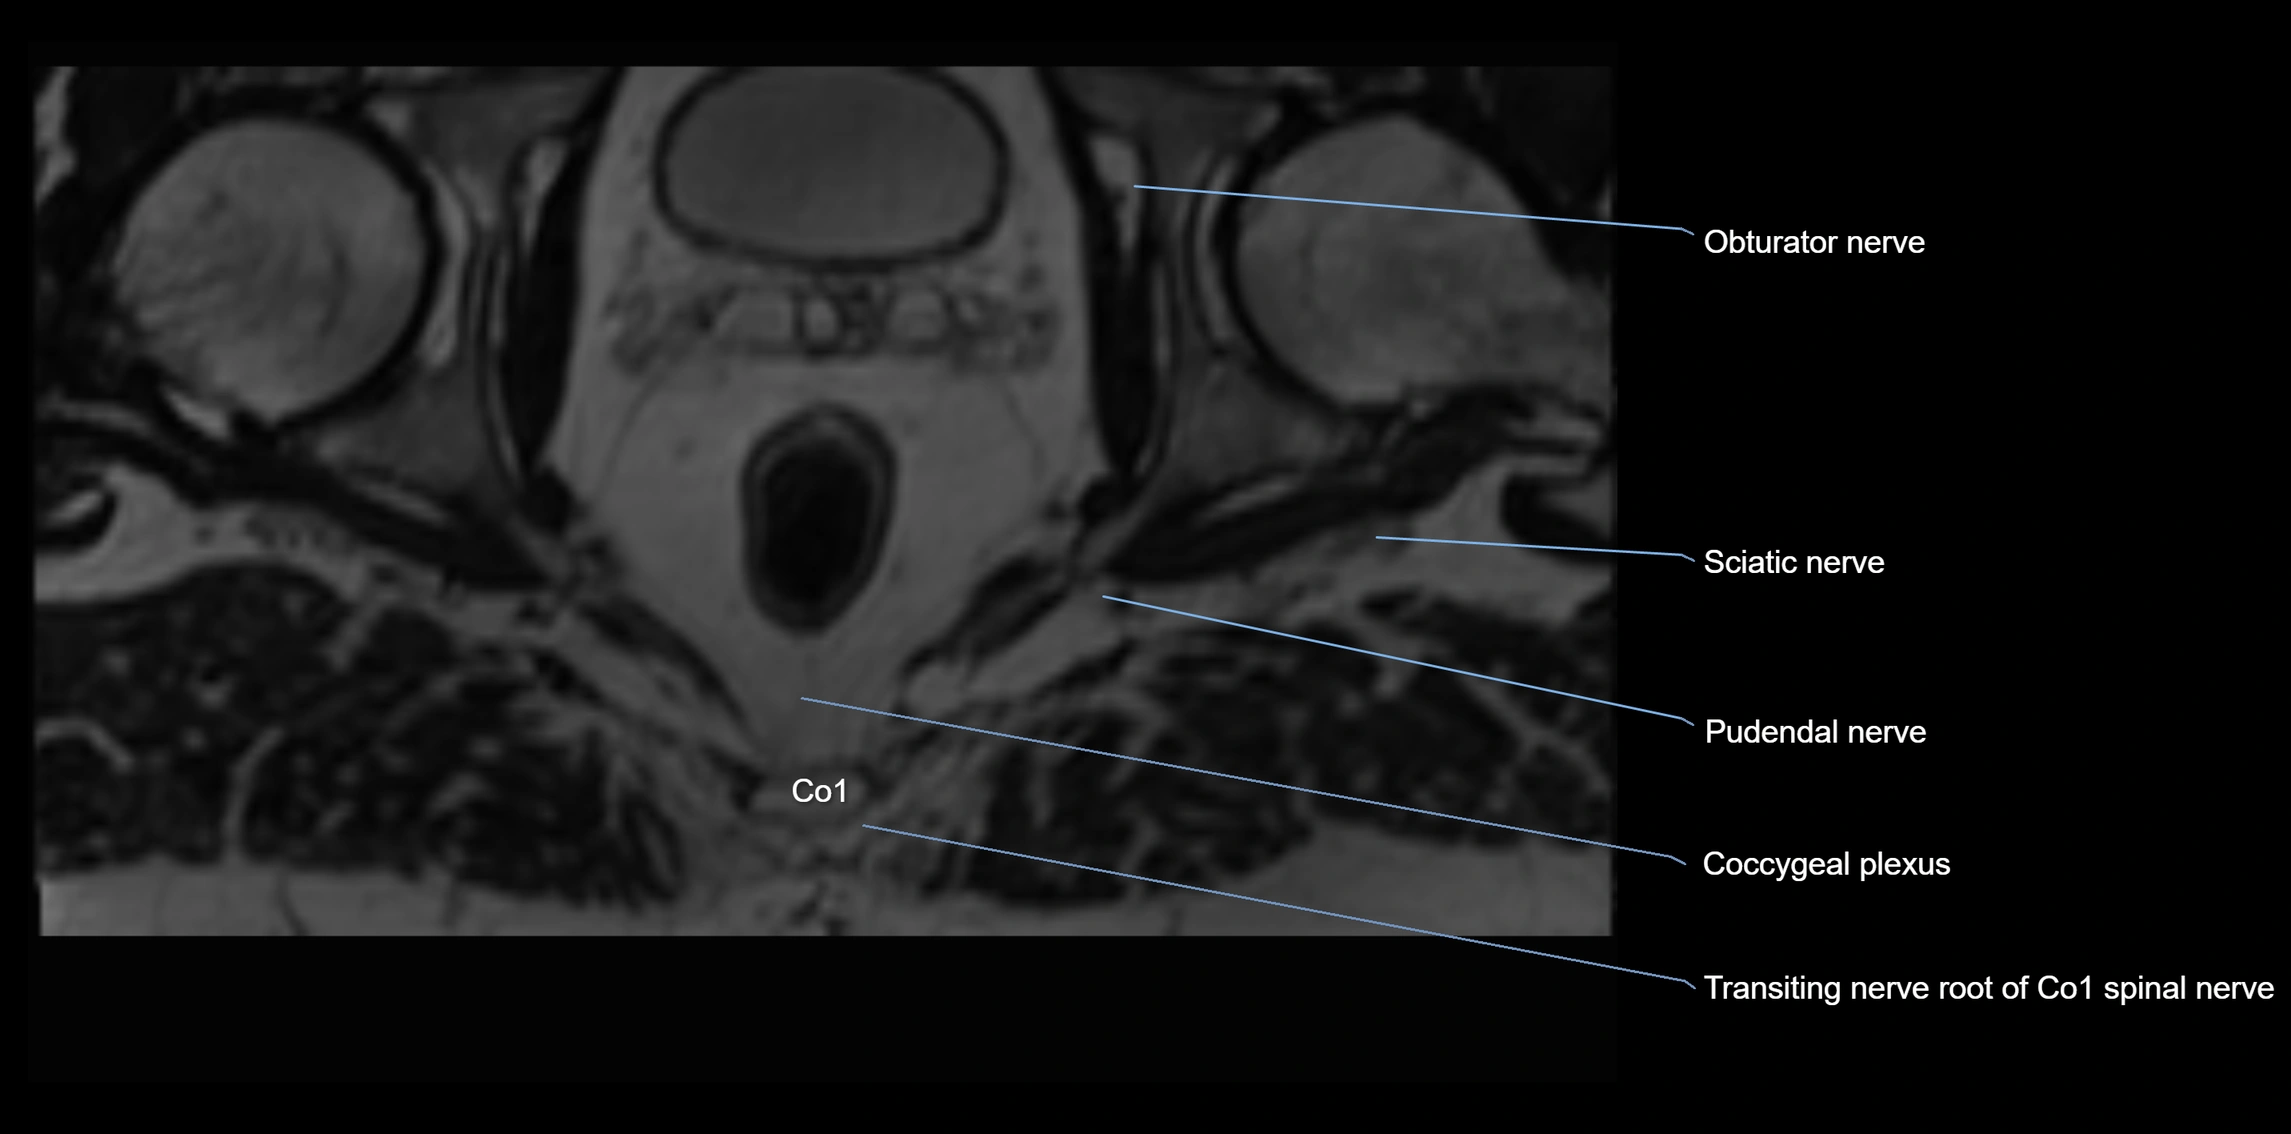

The anococcygeal nerve is a small sensory nerve derived from the coccygeal plexus, which itself is formed by the ventral rami of S4, S5, and the coccygeal nerve (Co1). Although tiny, this nerve plays an important role in supplying the skin of the coccyx and the area between the anus and coccyx. It passes through the sacrotuberous ligament and runs in the midline behind the coccyx.

Despite its small size, the anococcygeal nerve is clinically important because of its involvement in coccygodynia (coccyx pain) and perineal pain syndromes.

• Arises from the coccygeal plexus, formed by ventral rami of S4, S5, and Co1

MRI image

image